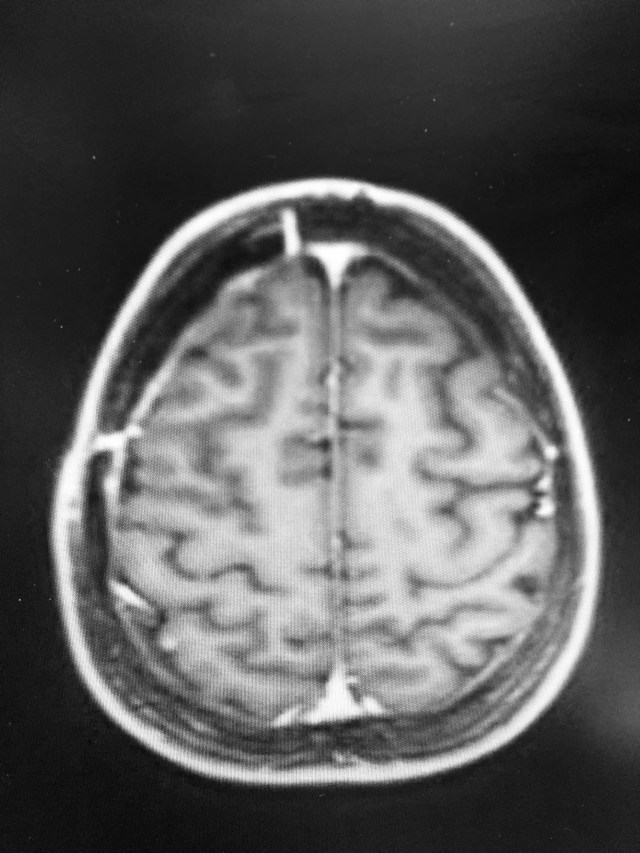

Getting to the meaning of the title of this blog. Upon my return from Europe in July, I had a brain MRI that showed a new tumor. I have not given it a true name this time. I refer to it as ‘Clarice’s baby’. I was diagnosed with brain metastases from my breast cancer in February this year. I had a scan in May and it was clear after the craniotomy and 10 treatments of radiation. This tumor is/was a very small baby tumor hiding in the back of my brain. A baby tumor so small that they actually missed it on my scan in May. Thankfully Baby Clarice has grown very slow and the required treatment this time was more radiation but a different kind, a much stronger radiation than last time. This one radiation treatment had more radiation than my last 10 treatments combined, by a lot. So much radiation in fact, that they had to partially sedate me for 3 days after because of the high risk of seizures. This treatment is referred to as cyber knife or gamma knife. The champagne is just because I’ve been drinking a lot of it recently!

Can you see it??

I thought I had a clear scan two months ago but when the doctors looked back, this new tumor was actually there. They just didn’t see it. The last two months and during my trip to Europe I’ve been on this no new tumor high and I have felt great emotionally and physically. With this new tumor and learning that it was always there I feel like I’ve been knocked down by Mike Tyson or whoever punches really hard. Less than a month after my surgery it grew. I think about what my oncologists have told me since the beginning, that the first 3 MRI’s are the most important and the most indicative of how the next 12 months of my disease will progress. It’s reoccurring quickly but slowly. So it’s good and bad. It’s ‘maintainable’ right now. I am devastated to be completely honest. I have been saying the whole time if I could just get like 6-12 months of clean scans I’d be really happy, just a little more time. I am reminded that this may not be my reality but I will still hope for it.